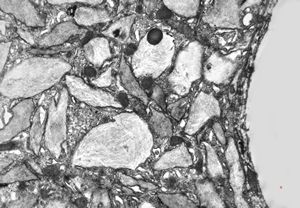

Whipple disease